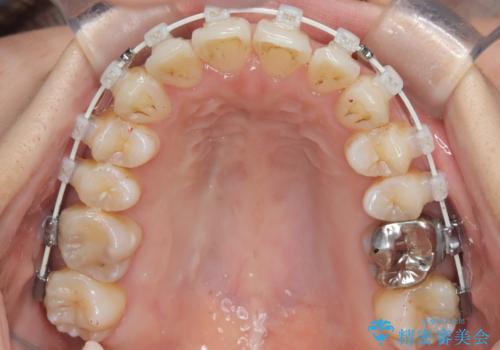

- 患者様は、上顎前歯の突出を改善したいとのご希望で来院されました。診断の結果、噛み合わせや全体的な歯列には大きな問題がないため、上顎のみを対象とした部分矯正が最適と判断しました。特に患者様は短期間での治療完了を希望されていたため、治療期間を約半年と設定しました。審美ワイヤーを用い、前歯を後方に移動させることで、自然で整った仕上がりを目指しました。治療計画は、患者様のスケジュールや希望を最大限考慮し、実現可能な目標を設定しました。

部分矯正では、治療範囲が限定されるため、力のコントロールが非常に重要です。本症例では、前歯を後方に移動させる際、周囲の歯や噛み合わせに影響を及ぼさないように細心の注意を払いました。また、短期間の治療でも歯の移動に伴う歯肉や歯根への負担を抑えるため、定期的なチェックと調整を行いました。患者様には矯正装置の清掃を徹底していただき、虫歯や歯周病のリスクを回避しました。結果として、予定通りの期間で治療を完了し、患者様には満足していただけました。